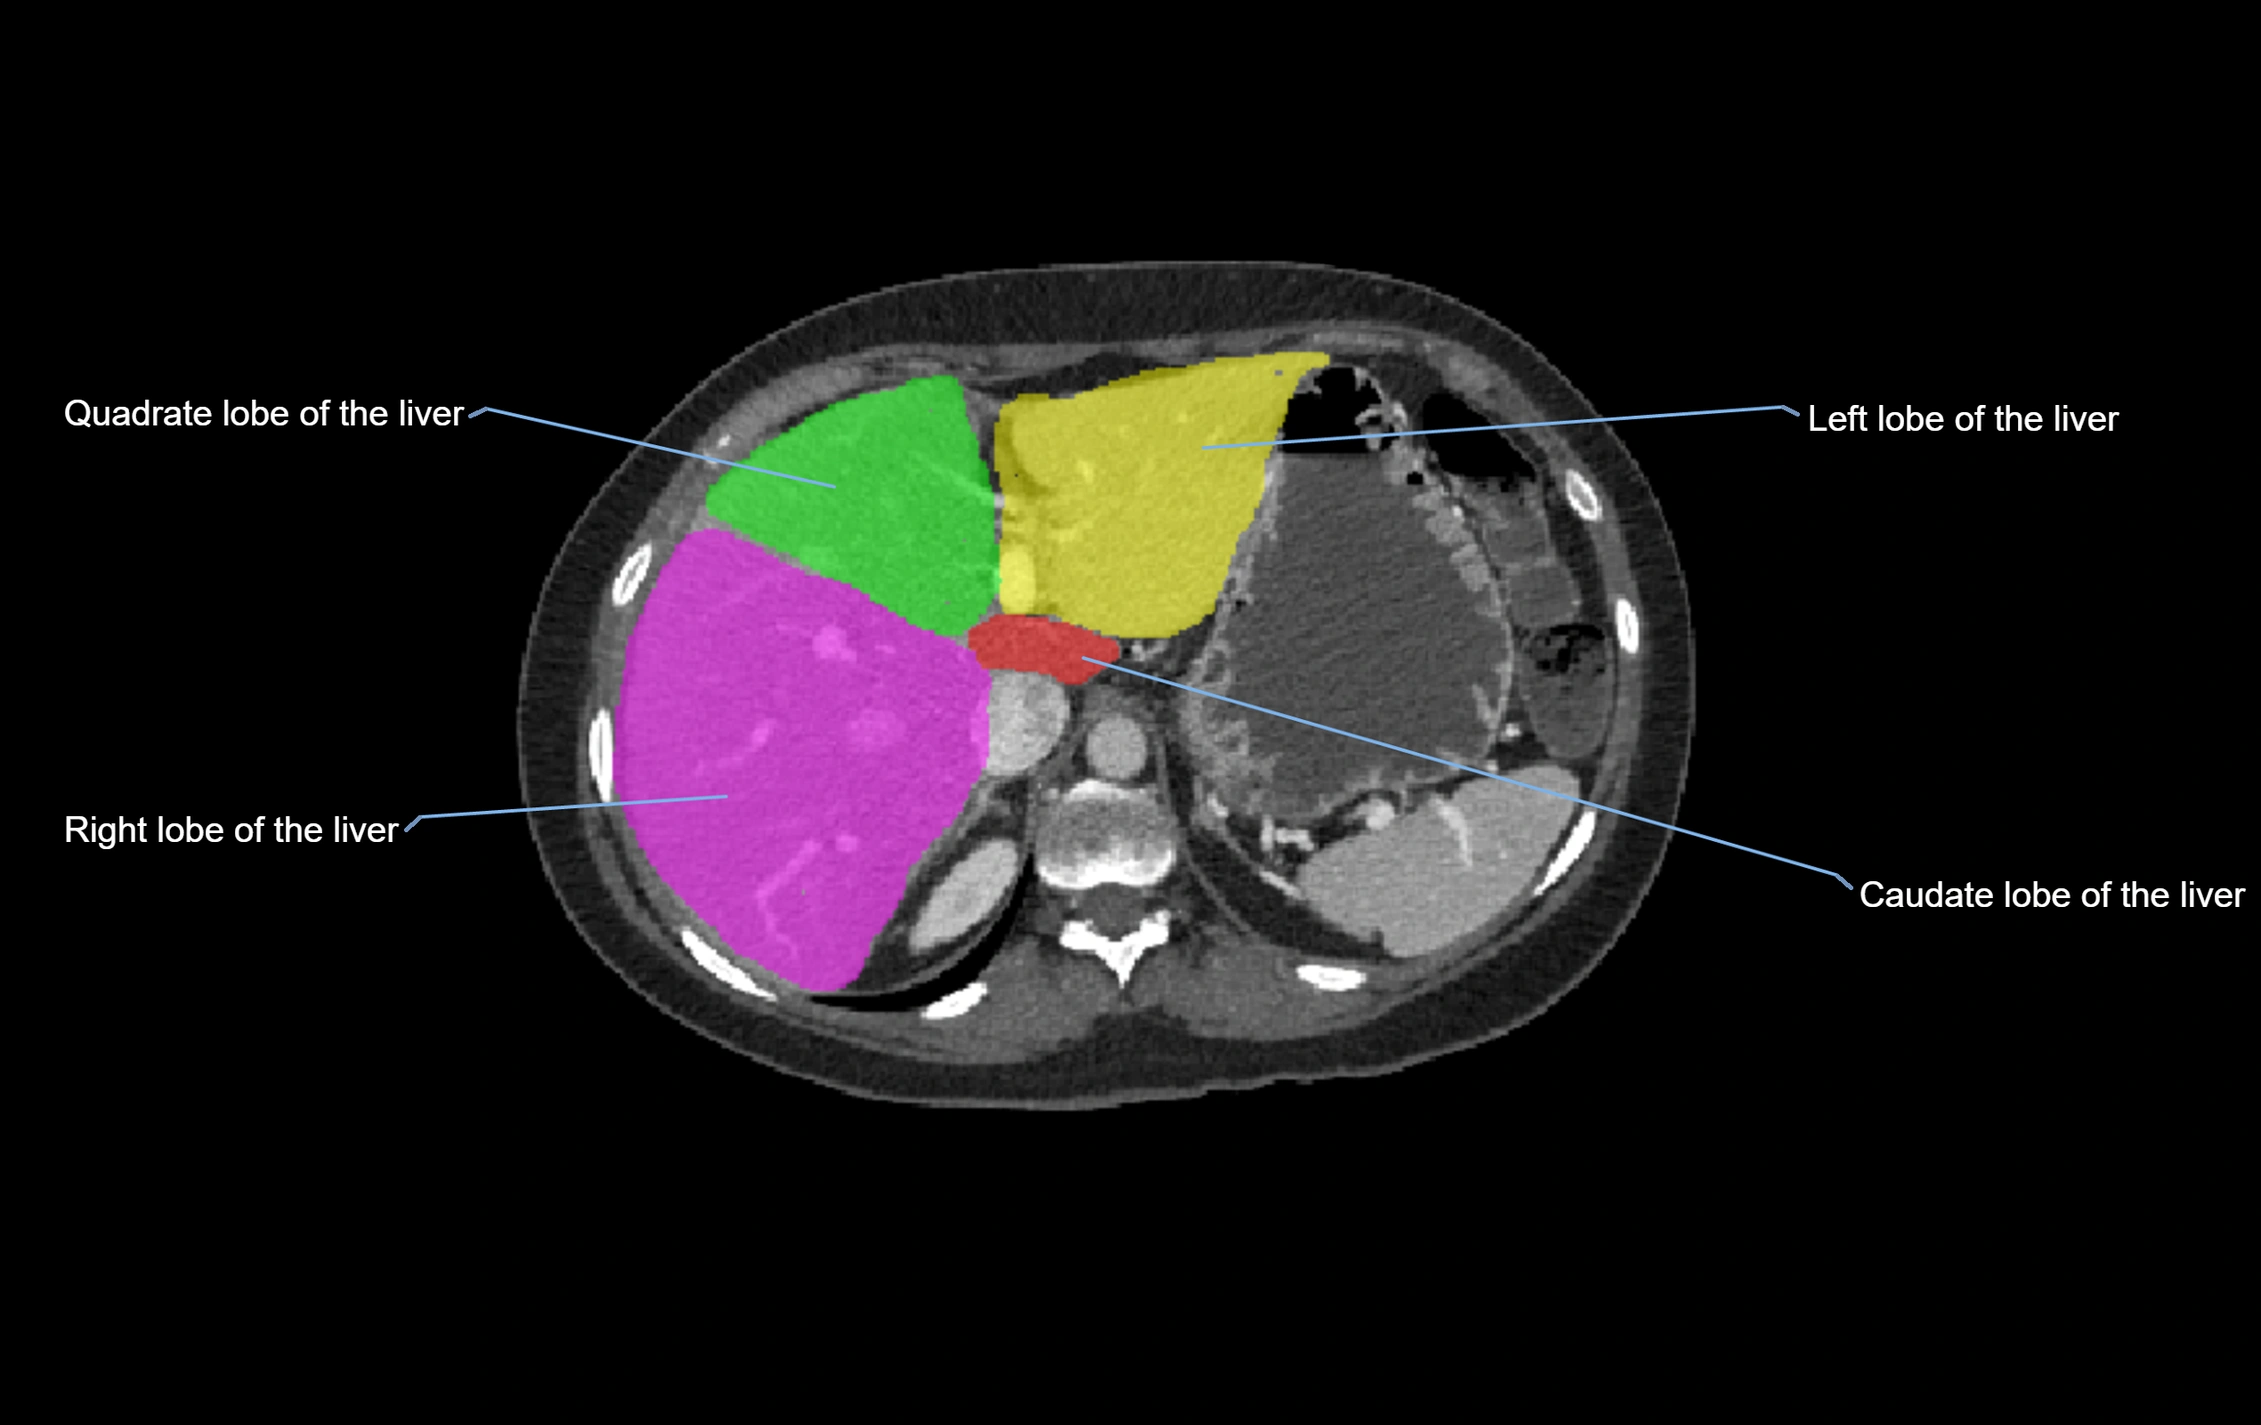

CT Image

image